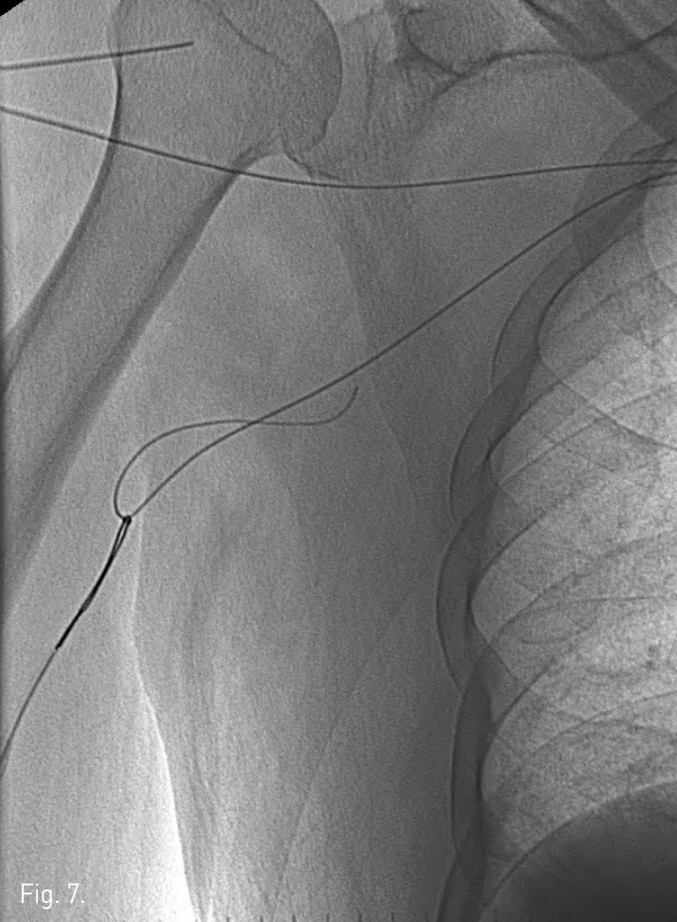

Fig. 7

The second guide wire is pulled out through the brachial access.